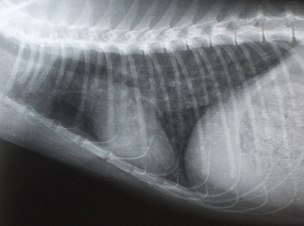

X線検査

気管支パターンが認められます。また横隔膜が斜めになり、暗い肺野の部分が多くなります。時に右の中葉や左の後葉に硬化像が認められます。

イメージ イメージ

Figure 2. 治療前のX線写真、肺のX線の透過性の亢進と気管支の肥厚を認める Figure 3. 治療3日後のX線写真、肺の透過性が低下(改善している)している。